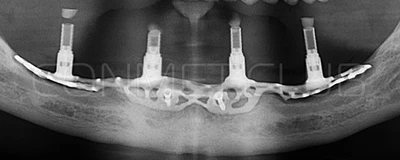

2. После этого произвели компьютерное моделирование самого имплантата и фиксирующих элементов. Примечательно, что в абатментах, использовался отлично зарекомендовавший себя и проверенный десятилетиями интерфейс КОНМЕТ! В результате получили несколько специальных файлов, позволяющих не только сделать сам имлантат, но еще до операции изготовить и сами зубы. Данные файлы передали в изготовление на специальном 3D оборудовании.

Имплантат напечатали из особого, биосовместимого, медицинского титана на предприятии имеющим соответствующую медицинскую лицензию. Толщина имплантата составила 0,8 мм, а вес всего несколько грамм!